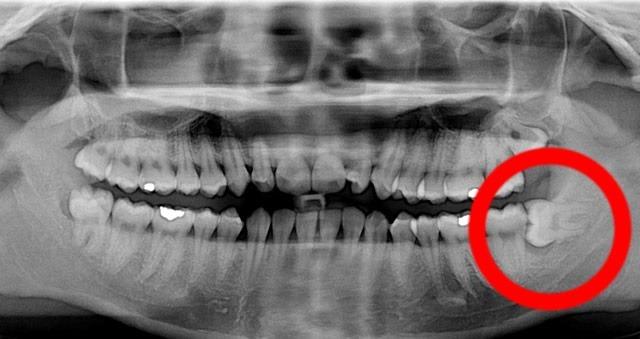

Las muelas de juicio se denominan así porque suelen doler desde que salen, alrededor de los 16 años, hasta que terminan de hacerlo, a veces hasta 10 años después. Debido al cambio de la dieta de los humanos desde hace unos 5000 años o más, se está dando una tendencia en el crecimiento de las mandíbulas, que va siendo menor, lo que dificulta aún más el crecimiento de las muelas, que muchas veces deben extraerse ya que apiñan hacia adelante (44% de los casos) o no brota completamente de la encía (38% de los casos).

La extracción de las muelas de juicio puede realizarse debido a varios factures, aunque siempre tiene que ver el impacto que tuvo o puede tener en una dentadura. Los principales motivos son el corrimiento de los dientes anteriores seguido a problemas de caries debido a la dificultad que genera cepillarse una muela sin brotar completamente, es por eso que la extracción siempre será objeto de un profundo análisis de parte del odontólogo. La extracción de las muelas no suele ser dolorosa, aunque debes tener en cuenta algunos detalles para no llevarte ninguna sorpresa. En este artículo conocerás mas sobre el tema y sobre el cuidado de tu boca una vez que te las hayan quitado.